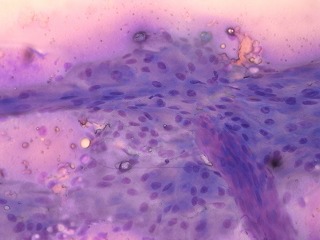

注射針での採材を試み、細胞集塊を採取。

細胞診の結果では、肛門周囲腺種の疑いであった。